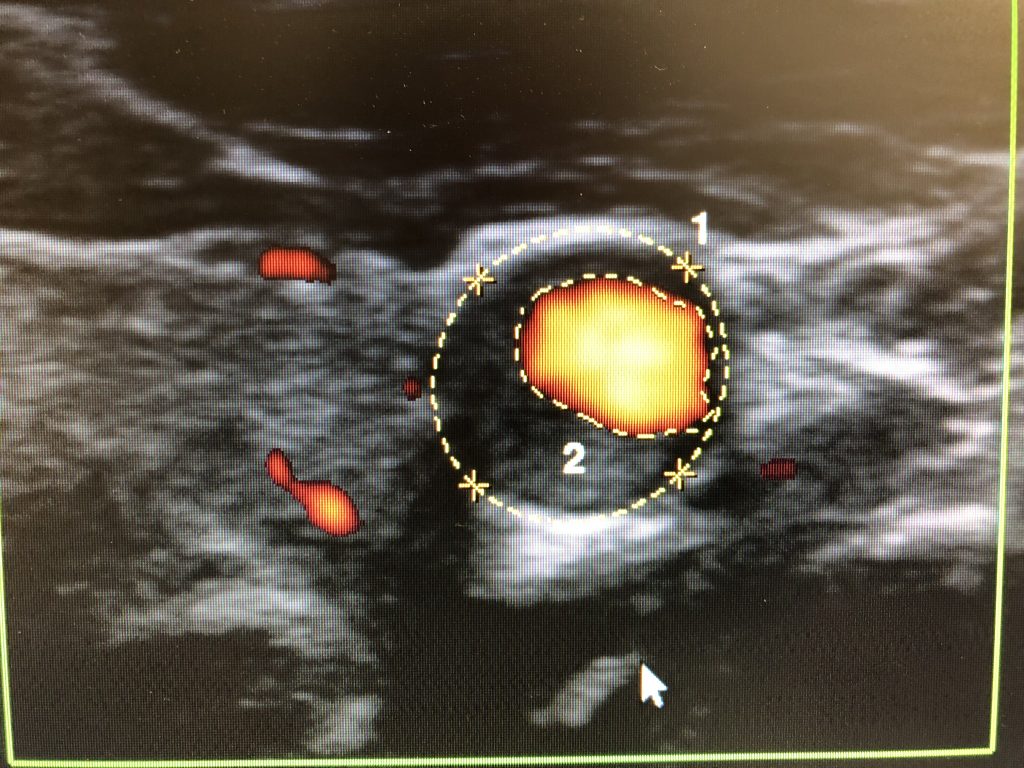

頸動脈超音波検査

この非侵襲的検査は音波を使用して血管内の血液の流れと圧力を測定します。

- 年に一度の頸動脈ドップラー超音波検査を受ける(以前に脳卒中を起こしたことがある場合)。これは、医師が頸動脈を通る血流を観察できる、短時間で痛みのない検査です。